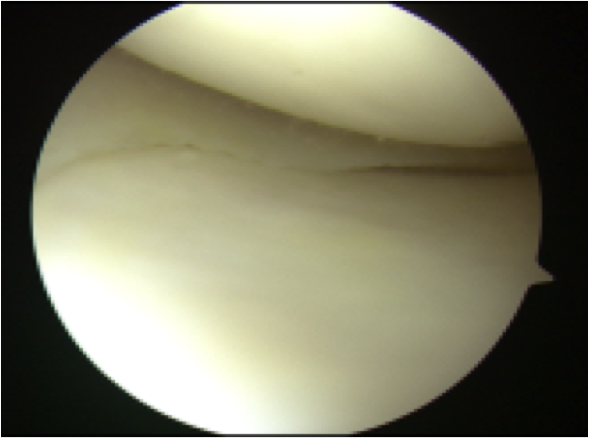

ACLは大腿骨付着でわずかに

残存するも、緊張は認めず

機能していない